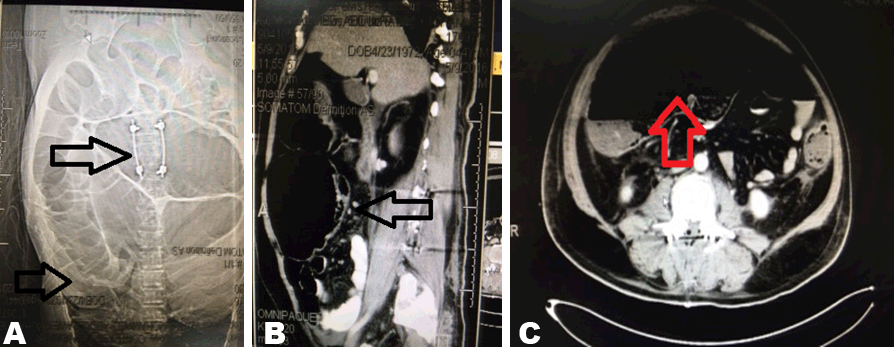

A 44-year-old Egyptian male; not known to have any medical problems before; was admitted as RTA victim. He had recently underwent operative fixation for unstable lumbar spinal fracture five days prior to surgery consultation. He had also a plaster cast applied to a fracture of left ankle. Patient had three-day history of progressive abdominal distension with diffuse pain, nausea and occasional nonbilious non bloody vomiting. Patient did not passed stools or flatus. On general examination, a bedridden obese male having stable vital signs and normal temperature. He was in pain, mildly dehydrated. Locally, the abdomen was diffusely distended with diffuse tenderness maximally over right lower quadrant with rigidity and positive rebound. A tympanic note was noted with sluggish bowel sounds. The rectum was empty. Labworks showed mild leukocytosis with elevated serum creatinine and urea. X-rays of the abdomen showed hugely distended colon. Volvulus then contrast enhanced abdominal and pelvic CT scan confirms the possibility of volvulus of cecum (Figure 1).

Figure 1: (A–C) Computed tomography abdominal scan showing hugely dilated colon down the rectum with cecal diameter exceeds 12 cm. Lumbar spinal fixation is also seen on (A).